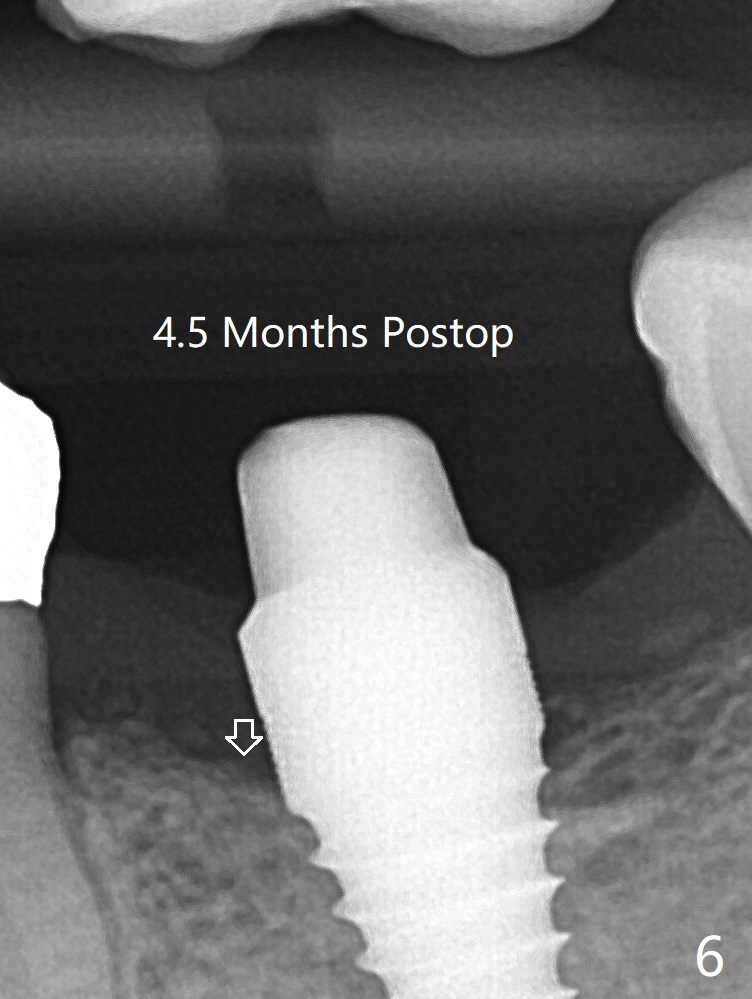

病人抱怨用临时牙冠咀嚼疼痛,不咬后没有不舒服,其实临时牙冠咬合面穿孔,牙龈正常,永久粘固剂没有外溢(图七)。术后4.5-6个月植体周围骨质吸收(图六,七:箭头)。牙槽嵴处钻洞应与植体直径一样才能减少骨质吸收。